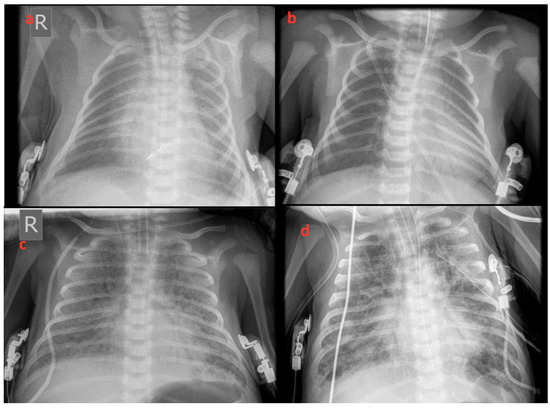

2. Case Report

3. Results